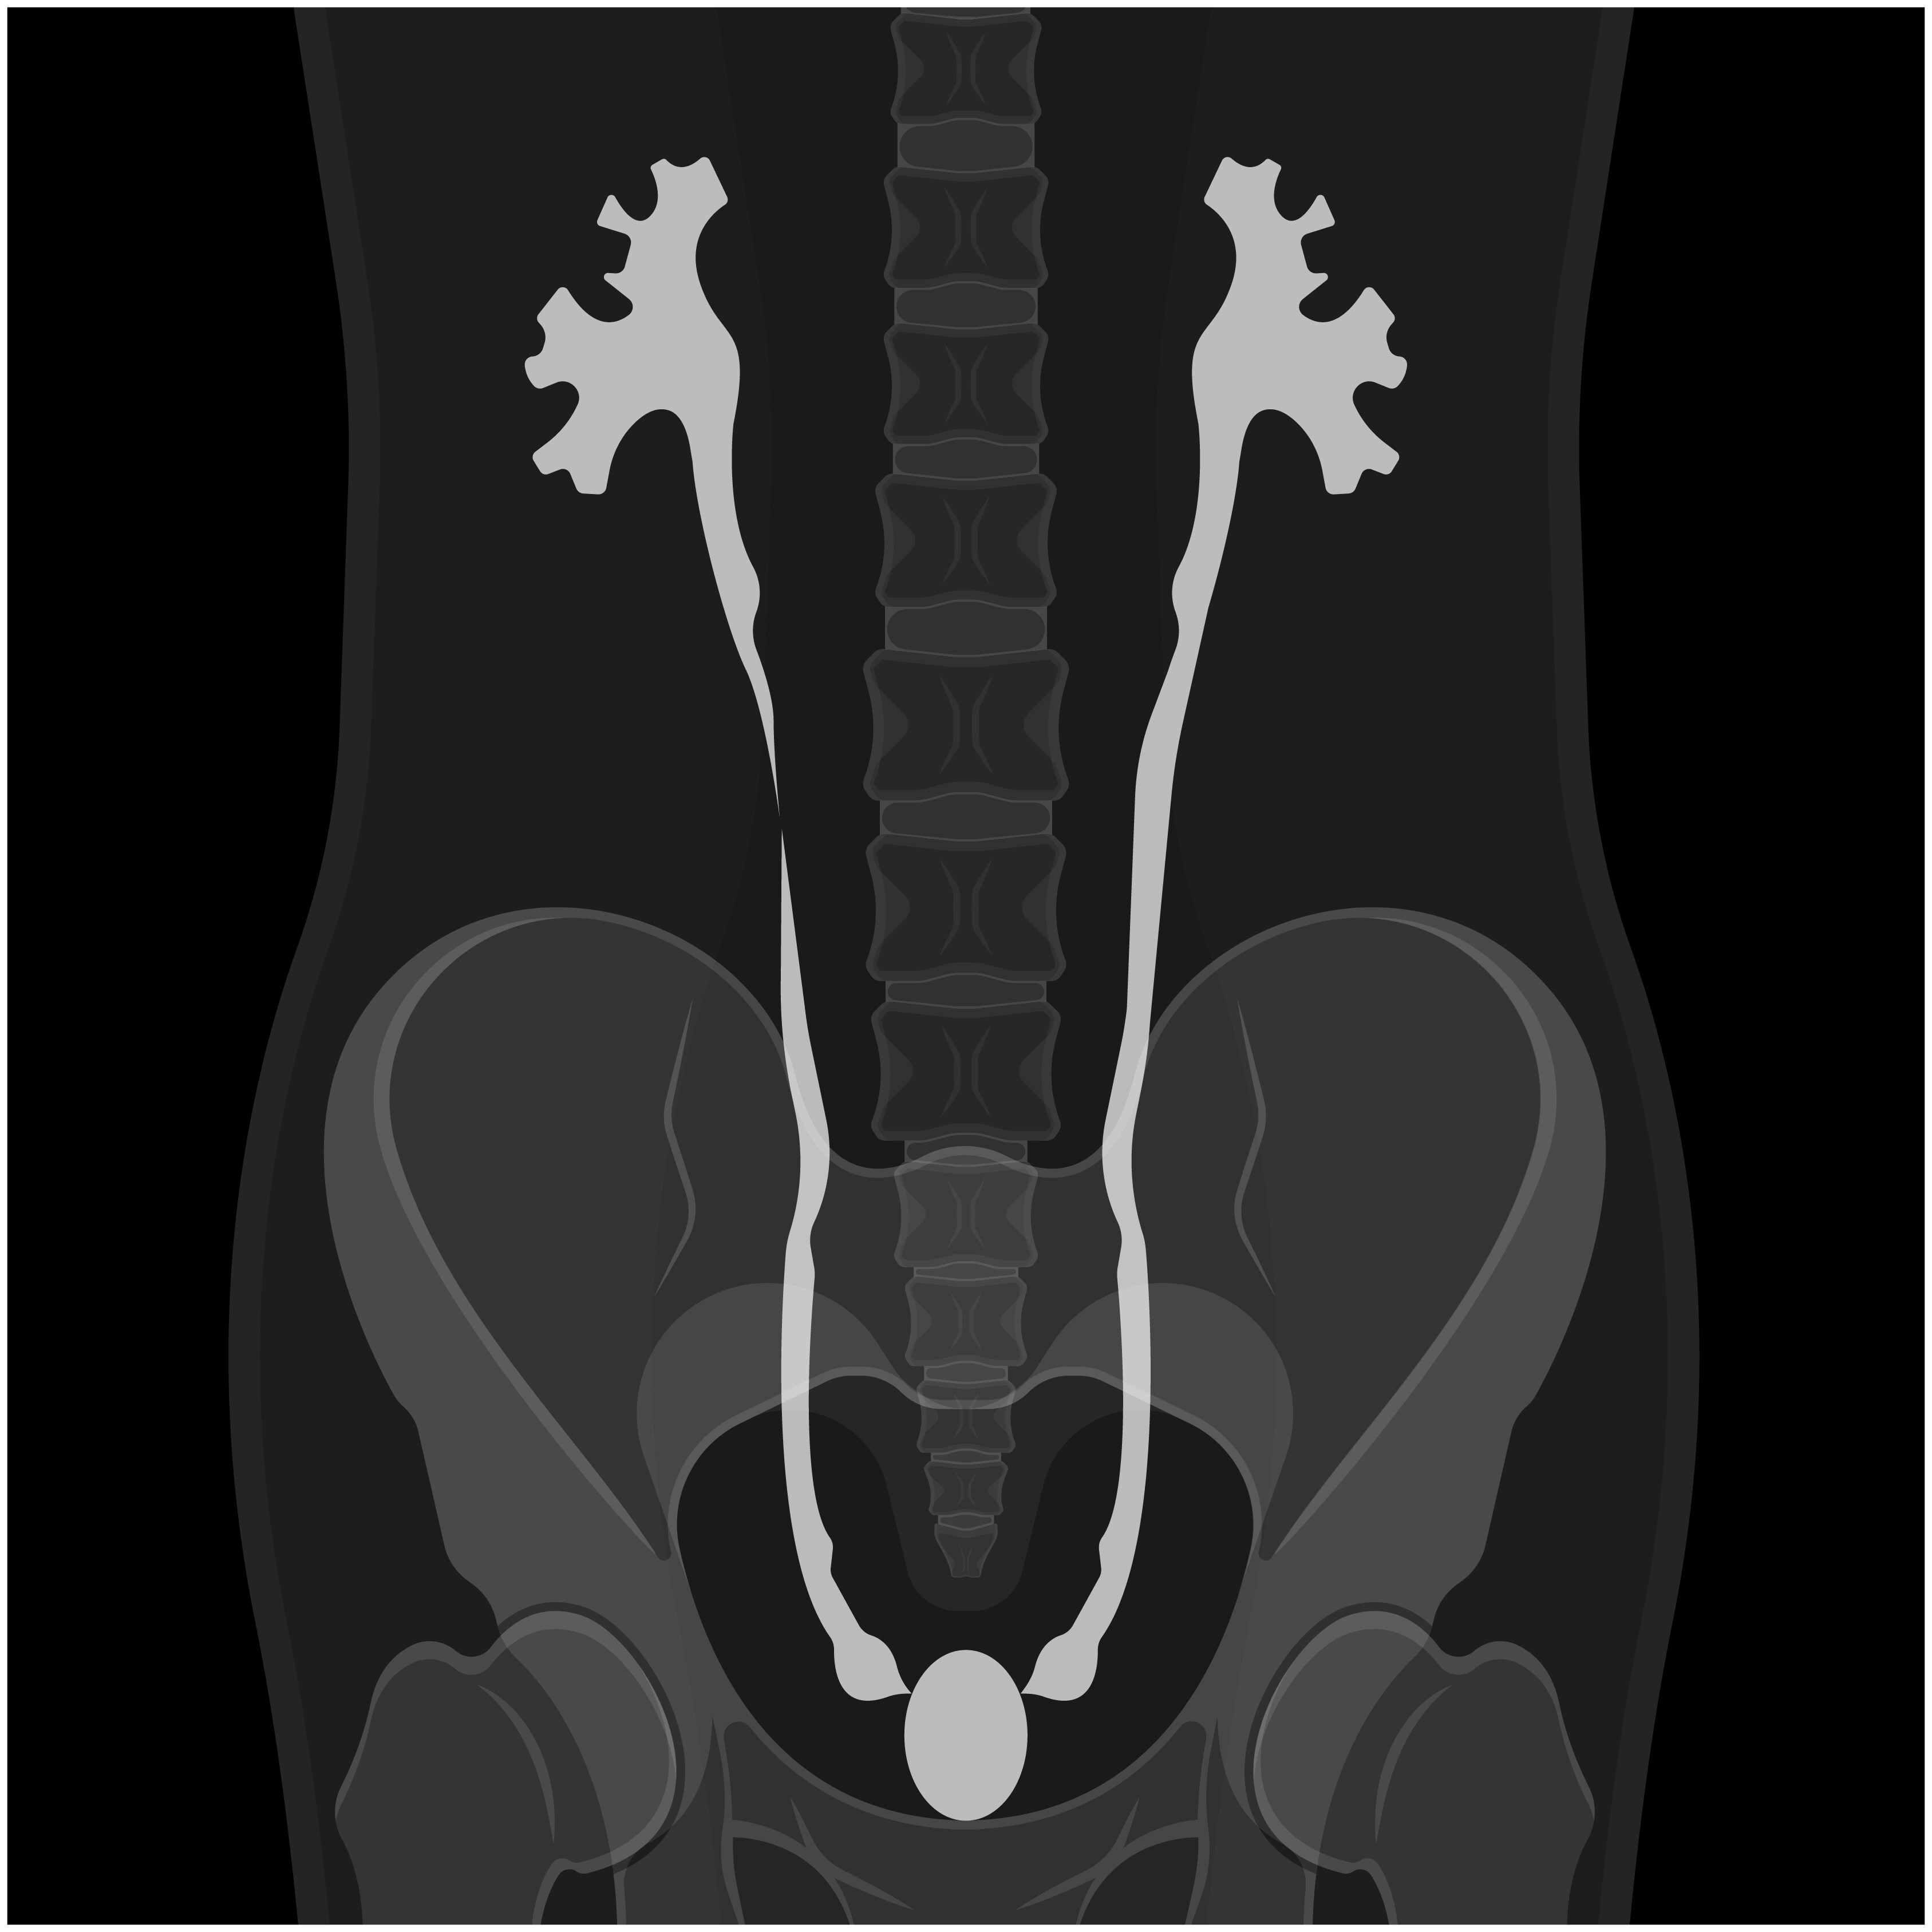

Urografía por tomografía computarizada (TC)

La urografía por TC es una TC de las vías urinarias, que incluye los riñones, los uréteres y la vejiga. Proporciona información detallada sobre el tamaño, la forma y la posición de cualquier tumor en las vías urinarias, incluida la vejiga. También puede revelar la presencia de ganglios linfáticos agrandados que podrían contener cáncer, así como otros órganos en el abdomen y la pelvis.¹

Pilografía intravenosa (intravenous pyelography, IVP)

Una IVP es una prueba de diagnóstico por imágenes en la que se le inyectará un tinte, y un radiólogo utilizará rayos X para observar el movimiento del tinte a través de las vías urinarias. Esta radiografía examina el sistema colector de los riñones para identificar cualquier irregularidad. Es eficaz para detectar pequeñas ubicaciones del cáncer y examinar las vías urinarias superiores, en particular los riñones, los uréteres y la vejiga.¹